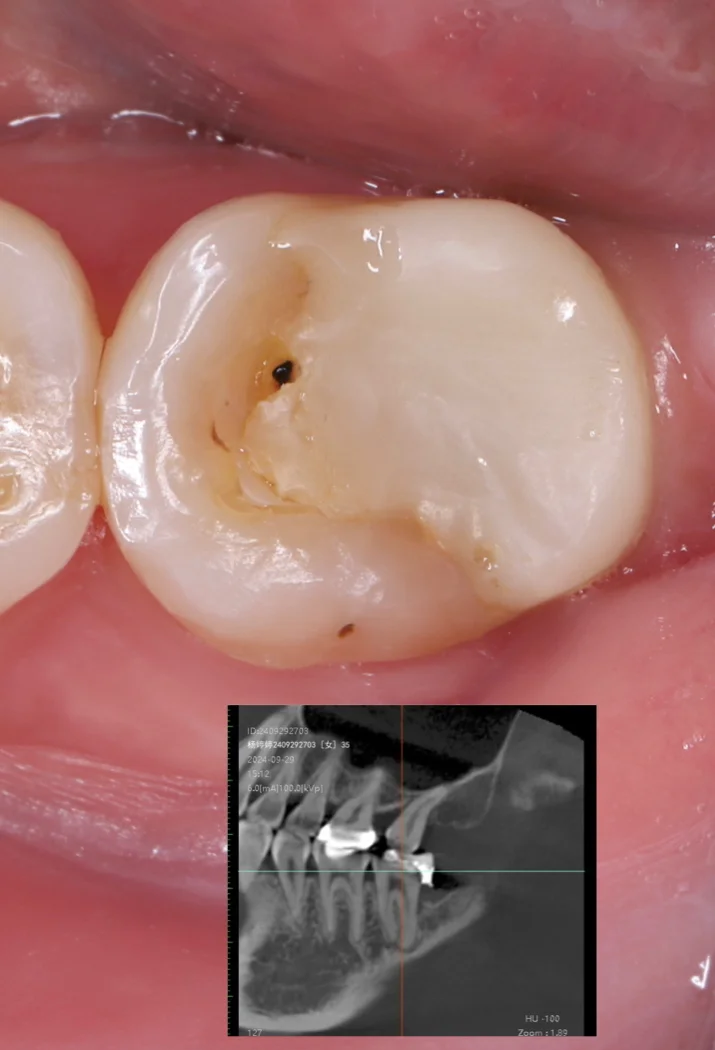

10、值得注意的是嵌体,尤其是贵金属嵌体,相对来说可以使用更长时间,且不容易发生继发龋但是贵金属嵌体价格昂贵,韩国普遍使用金合金嵌体来补后牙咬合面蛀牙,效果和持久度都很好,但是价格昂贵,在国内难以推广大多数人更喜欢颜色与牙齿相近的材料,如树脂或瓷如果说有一种蛀牙可以恢复健康,那只能是早期龋齿即牙面出现白斑一旦牙齿有。

13、值得注意的是嵌体,尤其是贵金属嵌体,相对来说可以撑久一点,不容易发生继发龋的状况但是贵金属嵌体价格不菲,韩国地区普遍使用金合金嵌体来补后牙咬合面蛀牙,效果和持久度都还不错,不过就是bling bling 的,在国内不好推广大家普遍喜欢和牙齿颜色相近的材料,如树脂或瓷如果说有某种蛀牙可以恢复。